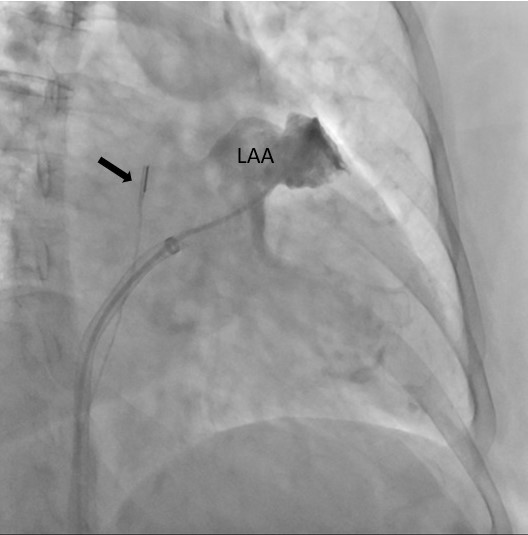

Specjaliści z Pracowni Kardiologii Inwazyjnej I Kliniki Kardiologii UCK przeprowadzili 3 zabiegi zamknięcia uszka lewego przedsionka (ang. LAAO – left atrial appendage occlusion) z wykorzystaniem systemu echokardiografii wewnątrzsercowej (ang. ICE – intracardiac echocardiography).

Zabiegi LAAO wykonuje się u pacjentów z migotaniem przedsionków i wysokim ryzykiem udaru niedokrwiennego mózgu, którzy nie mogą stosować leczenia przeciwzakrzepowego z powodu wysokiego ryzyka powikłań krwotocznych. Rutynowo przeprowadzane są one pod kontrolą echokardiografii przezprzełykowej (ang. TEE – transoesophageal echocardiography).

– U części pacjentów kwalifikowanych do LAAO ryzyko związane z wykorzystaniem obrazowania metodą TEE jest zbyt wysokie ze względu na poważne zmiany chorobowe przełyku. To dotychczas uniemożliwiało wykonanie zabiegu. Obrazowanie metodą ICE pozwala na bezpieczne wykonanie zabiegu zamknięcia uszka lewego przedsionka również w tej grupie chorych, ponieważ specjalną sondę ultrasonograficzną wprowadza się nie do przełyku, lecz przez układ żylny pacjenta, bezpośrednio do jam serca – mówi dr Dariusz Ciećwierz, koordynator Pracowni Kardiologii Inwazyjnej I Kliniki Kardiologii UCK z I Katedry i Kliniki Kardiologii GUMed. – Dodatkową korzyścią tego rozwiązania jest większy komfort pacjenta w trakcie zabiegu, dzięki czemu można uniknąć sedacji czy znieczulenia ogólnego.

W ramach przygotowania do wprowadzenia metody do praktyki klinicznej w UCK, zespół zabiegowy miał możliwość przetrenowania jej zastosowania na zaawansowanym symulatorze w Centrum Symulacji Sercowo-Naczyniowej GUMed. Zabiegi wykonano u dwóch pacjentów z zaawansowanymi żylakami przełyku z powodu marskości wątroby oraz u pacjentki z wrodzoną naczyniakowatością krwotoczną (choroba Rendu-Oslera-Webera). Nadzór merytoryczny w trakcie pierwszych przeprowadzonych zabiegów zapewnił dr hab. Witold Streb, kardiolog ze Śląskiego Centrum Chorób Serca w Zabrzu.